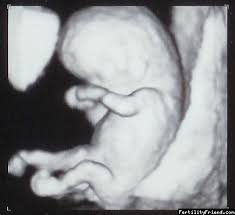

Your customizable and curated collection of the best in trusted news plus coverage of sports, entertainment, money, weather, travel, health and lifestyle, combined with outlook/hotmail, facebook. Embryo je dobre vyvinuté, telo má štruktúru a podobu ľudského tela, pretrváva naďalej nepomer medzi hlavovou časťou a telom. If a value is present, ispresent() will return true and get() will return the value.

visit full article here : https://www.babyweb.cz/8-tyden-tehotenstvi-vyvoj-plodu-tehotenske-zmeny His formidable technique and willingness to push boundaries inspired musicians and changed what people thought could be done. Otehotnela som hned po vysadeni antikoncepcie ktoru som brala asi 6 rokov a teda teraz som cakala na. Práve ste sa prehupli do 8.

Hlava je stále nepomerne väčšia k telu a tvorí takmer polovicu dĺžky embrya.